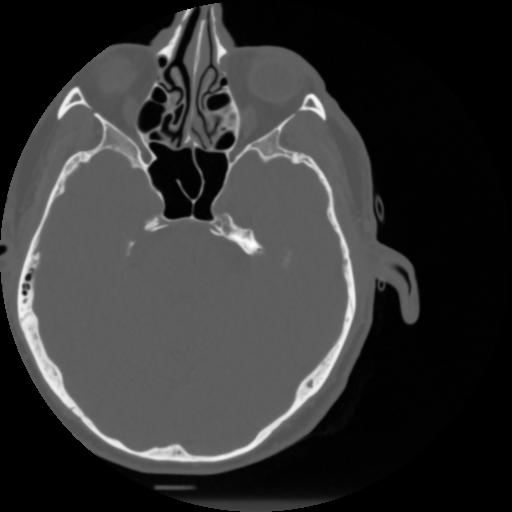

4 CEREBRO,,Vol,0.5,CEREBRO,,